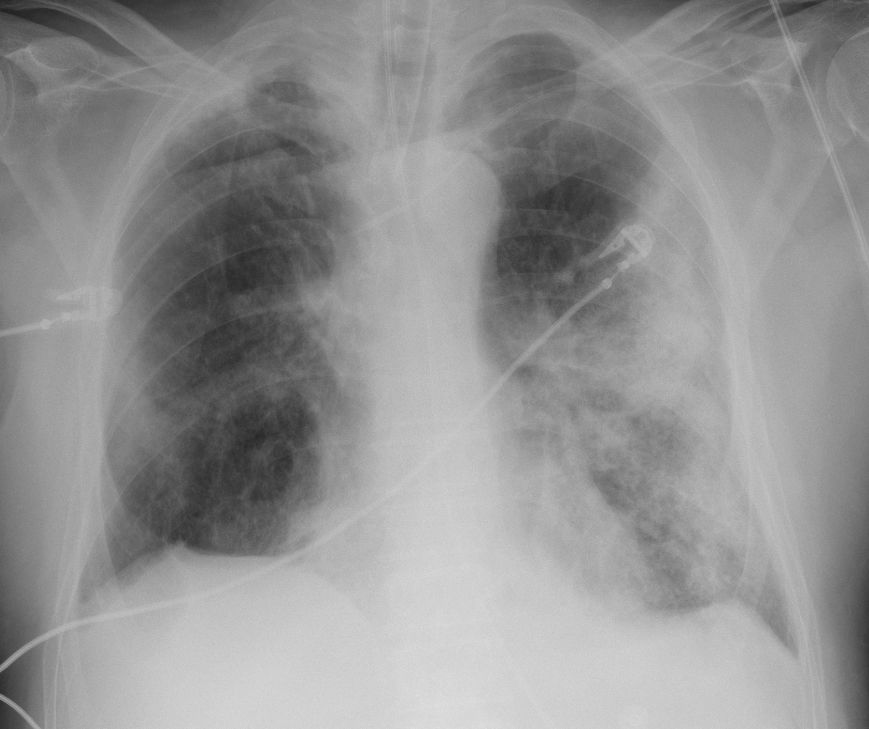

비강이나 폐 상부 등 상부 호흡기가 감염되면 염증 반응이 나타나고, 이는 기침과 재채기를 유발해 바이러스의 확산을 부추긴다. 기도 하부가 감염될 경우 호흡 곤란 등 치명적인 합병증으로 이어질 수 있다.

68세 중증 환자의 엑스레이 사진으로, 폐의 흰 부분은 염증을 의미한다 (자료: 영국 왕립방사선학과대학)